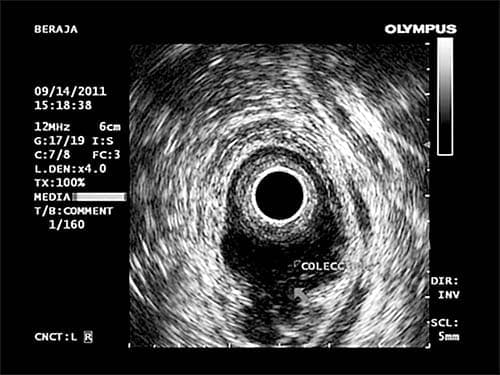

Permite valorar lesiones que pueden estar en el interior del recto, como pólipos o tumores, o en sus paredes, como lesiones de los esfínteres anales y musculatura del suelo pélvico, prolapso rectal, etc., o por fuera de la pared del ano y recto, como inflamaciones (abscesos), fístulas, y otras patologías.